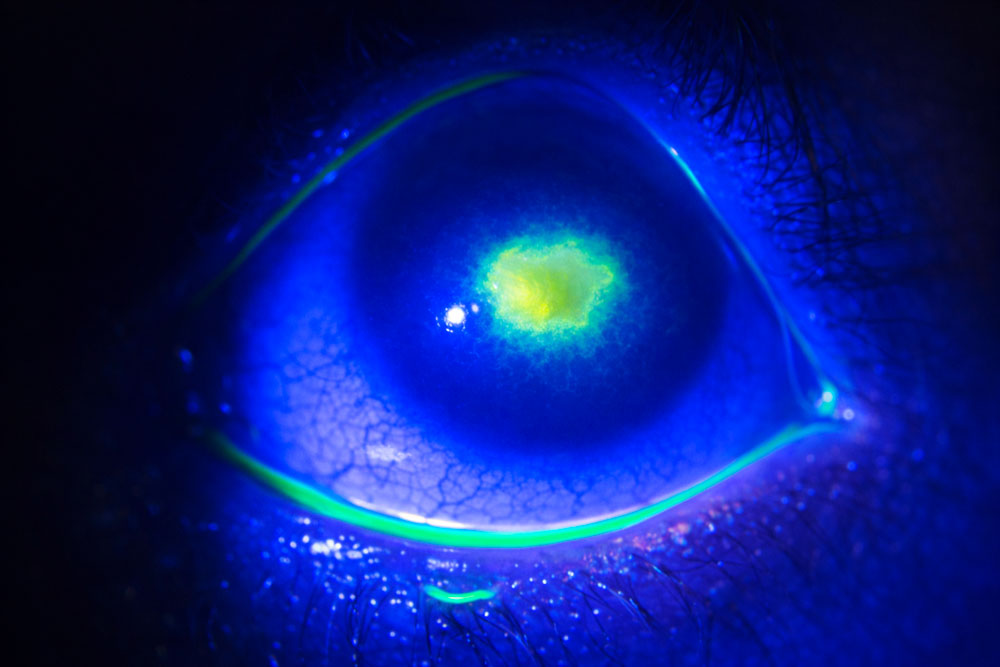

Ulcère de cornée post-traumatique

Un ulcère cornéen post-traumatique est une plaie de la cornée survenant après un choc ou une blessure : coup d’ongle, branche, poussière, projection métallique, lentille de contact.

Même si la lésion peut sembler superficielle au départ, elle expose à un risque d’infection et de cicatrice définitive de la cornée.